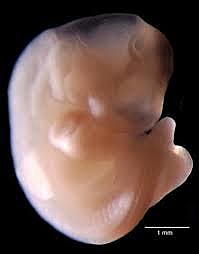

• Caracterización

35

Caracterización

El embrión ya tiene características humanas evidentes